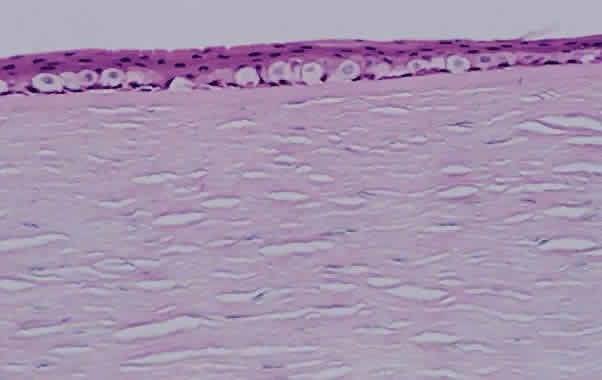

Much attention has been given to the histopathologic nature of the “snowbanks,” which has been studied by both light and electron microscopy.52,54,56–58 These fibrovascular-glial proliferations are found over the inferior pars plana and peripheral retina. They are composed of dense connective tissue derived from condensed, collapsed vitreous and often are vascularized. These vessels may reveal features of high endothelial venules (Fig. 8). Such endothelia are known to play a role in the homing of activated lymphocytes.54 The cellular elements of these membranes include fibroglial cells that are believed, based on their electron microscopic characteristics, to represent fibrous astrocytes, as well as nonpigmented ciliary epithelial cells, fibroblasts, and lymphocytes (Fig. 9).52–55,59,60 The vitreous is infiltrated by chronic inflammatory cells, and despite the nongranulomatous nature of the inflammatory component in the snowbanks, vitreous snowballs have been reported to consist of epithelioid cell granulomas.52

Fig. 8. Electron micrograph from eye with pars planitis (see also Fig. 9) showing collagen deposition and high endothelial venules (arrow).

Fig. 9. A. Photomicrograph of “snowbank” in patient with pars planitis showing a fibroglial mass with proliferated epithelial elements (hematoxylin and eosin; × 31). B. Higher magnification showing epithelial elements and glial proliferation (hematoxylin and eosin; × 80). C. Chronic inflammatory cell infiltrate in pars planitis (hematoxylin and eosin; × 200).